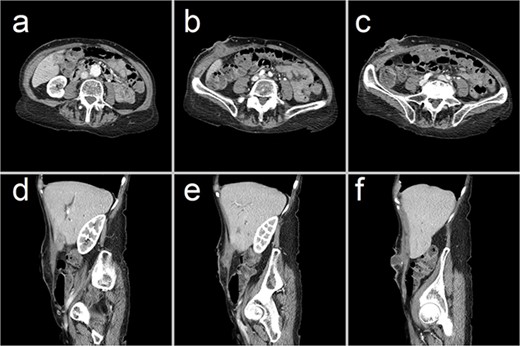

A 75-year-old woman from a nursing home presented to the emergency department with a 3-week history of a painful right-sided abdominal lump. She was otherwise systemically well. Her medical history was notable for end-stage chronic obstructive pulmonary disease requiring permanent home oxygen, lung cancer, and chronic cholecystitis. On presentation, all her vitals were normal. Examination revealed an indurated, tender, irreducible mass in the right hypochondrium with overlying cellulitis. Her white cell count was 9.3 mmol/L and C-reactive protein was 45 mg/L. CT scan revealed a complex collection in the right anterior abdominal wall, contiguous with a thickened gallbladder, consistent with an abdominal wall abscess complicating perforated acute-on-chronic cholecystitis (Fig. 1).

Representative CT images showing (a–c) axial and (d–f) sagittal views of a 47 × 23 × 66 mm complex collection within the right anterior abdominal wall, consisting of fluid and phlegmonous components. This collection is contiguous with a thick-walled gallbladder that contains calculi. These findings are consistent with an abdominal wall abscess complicating acute-on-chronic cholecystitis with extraperitoneal perforation.